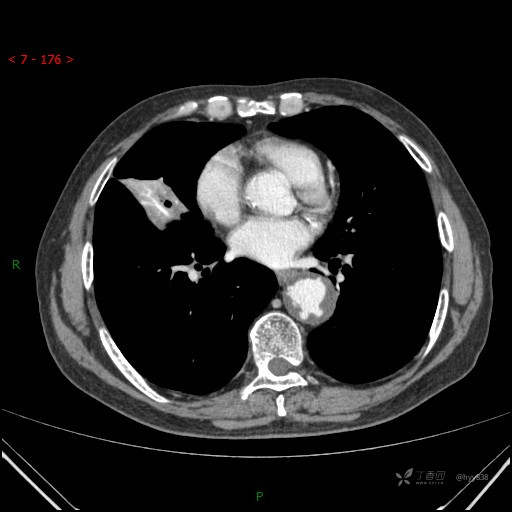

静脉期